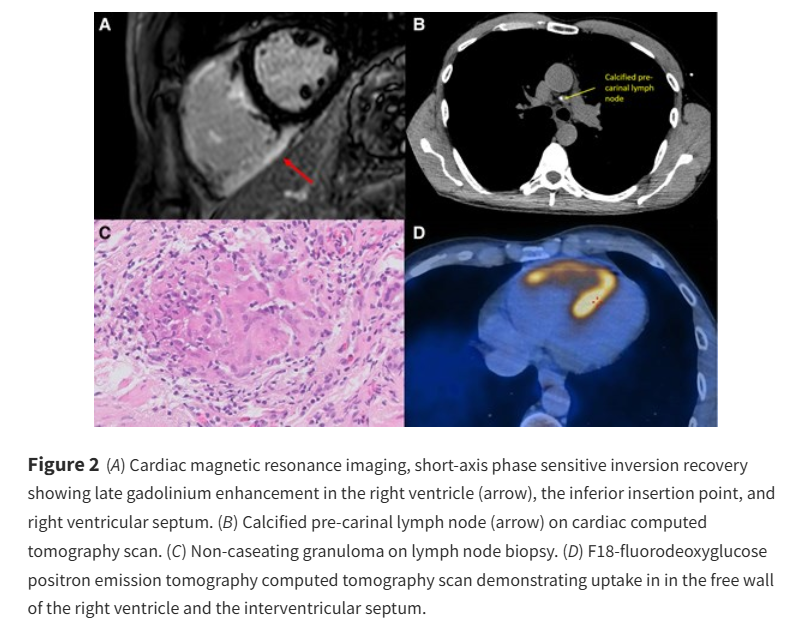

The challenging diagnosis of ARVC - is imaging the key? ow.ly/Nqpk50VSn9a #EHJCaseReports Philipp Sommer Tee Joo YEO Aaysha Cader Boldizsar Kovacs Erik Rafflenbeul A.Nazmi Calik Obayda Azizy Sara Moscatelli EHJCaseReports Editor-in-Chief #CardioX #EPeeps